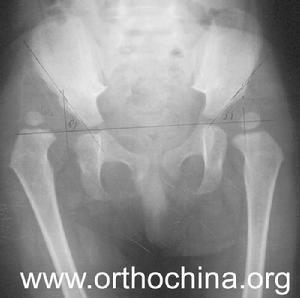

2.Perkin象限

股骨頭骨骺核骨化出現後可利用Perkin象限判斷髖關節的脫位情況。即在兩側髖臼中心間連一直線,稱為H線,再從髖臼外緣向H線做一垂線(P線),將髖關節劃分為四個象限,正常股骨頭骨骺位於內下象限內,在外下象限時為半脫位,在外上象限內時為全脫位。

3.髖臼指數

從髖臼外緣向髖臼中心連線,其與H線相交所形成的銳角,稱為髖臼指數,其正常值為20°~25°。小兒開始步行後,此角逐年減小,至12歲時基本恆定於15°左右。髖關節脫位時此角明顯增大,甚至在30°以上。

4.CE角

也叫中心邊緣角(centeredgeangle)。即股骨頭中心點至YY'線的垂線與髖臼外緣和股骨頭中心點的連線所形成的夾角。其意義是檢測髖臼與股骨頭的相對位置,對髖臼發育不良或髖關節半脫位的診斷有價值。正常為20°以下。

5.Shenton線

正常時,閉孔上緣弧形線與股骨頸內側弧形線相連形成一條連續的弧線,稱為Shenton線,髖關節脫位時此線中斷。

6.Simon線

是髂骨外側緣至髖臼的外上緣,然後向下、向外,沿股骨頸外緣形成一條連續的縱弧線。髖關節脫位時,此弧線也中斷。